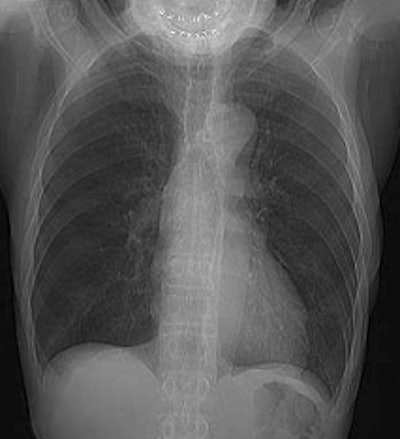

Intense right colon activity: Note the intense activity in the right colon in this asymptomatic patient. Increased activity in the right colon can sometimes be seen. Note uptake in the patients left upper lobe lung cancer. Focal activity in the left upper abdomen was related to the stomach. |